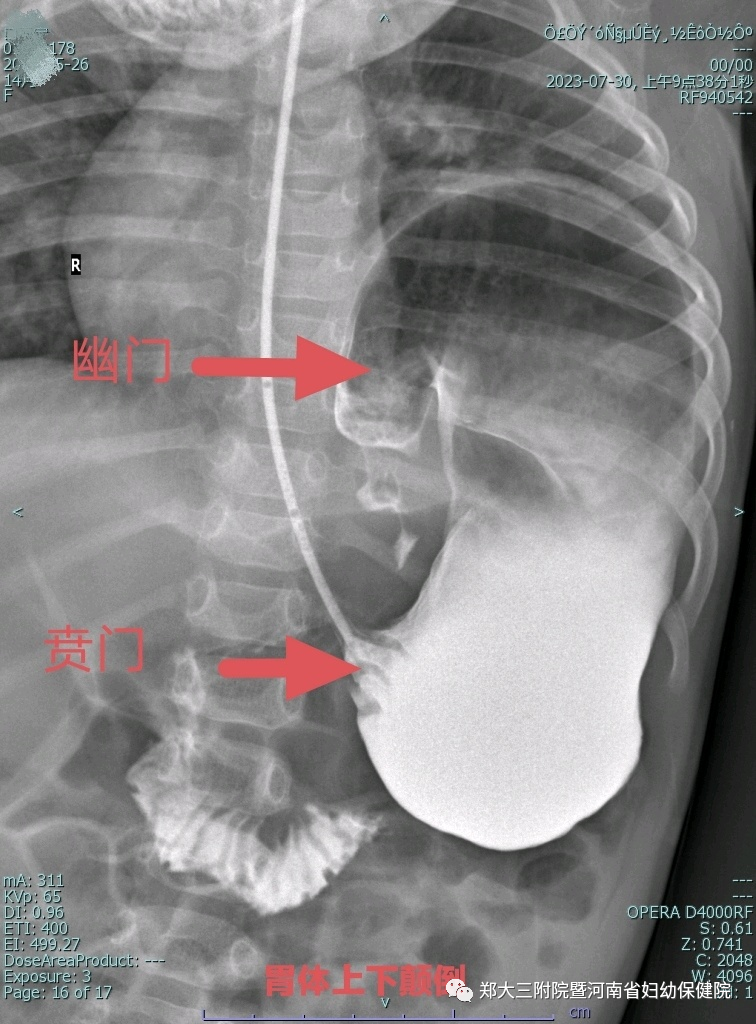

进一步完善造影检查才发现真正元凶——左侧膈膨升并完全性胃扭转。

患儿左侧胸腹间膈肌薄弱,胃体头低脚高翻了上去,形成一种完全性网膜轴型胃扭转。这才是导致患儿急性胃扩张的真凶。

术后消化道造影提示胃体恢复至正常位置。

杜俊鹏介绍:先天性膈膨升以右侧多见,左侧很少发生,同时合并完全性胃扭转并急性胃扩张则极为罕见。很多医生都很少见如此彻底的上下颠倒的胃扭转,这也是该患儿没有暴饮暴食但莫名出现急性胃扩张的原因。